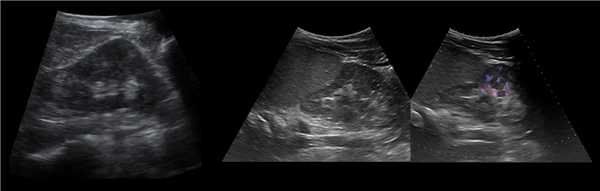

В положении пациента на спине по среднеключичной и переднеподмышечной линии выводим правую почку в соседстве с печенью, а левую почку вблизи селезенки. Оцените эхогенность почек. Корковый слой почки в норме изо- или гипоэхогенный по отношению к печени и гипоэхогенный по отношению к селезенке.

Рисунок. Эхогенность органов сравнивают на одном срезе. На УЗИ нормальная почка по соседству с печенью (1) и селезенкой (2). У детей до 6 месяцев паренхима почек в норме может быть гиперэхогенной по сравнению с печенью (3).

Чтобы увидеть верхний полюс почки, попросите пациента сделать глубокий вдох. Форма почки бобовидная — выпуклая с латеральной и вогнутая с медиальной стороны. Как вариант нормы расценивают эмбрионально-дольчатую почку, а так же горбатую левую почку.

Рисунок. Можно встретить горбатую левую почку — выпуклый неровный наружный контур из-за гипертрофии паренхимы в средней трети почки. Считают, что «горб» формируется у плода под давлением нижнего края селезенки.